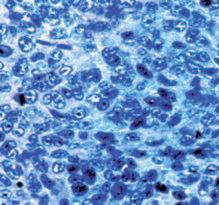

Questo meccanismo si manifesta come mostrato nella pagina a fianco: un gruppo di cellule del cancro al seno sono intrappolate all'interno della vena porta epatica.

Una volta che queste cellule invadono il tessuto epatico, un ‘tumore al seno’ si diffonde ora all'interno di un altro organo, in questo caso il fegato.

Immagine al microscopio di cellule tumorali del seno (la massa di cellule marroni al centro) che nel fegato (struttura blu nello sfondo) formano una metastasi.